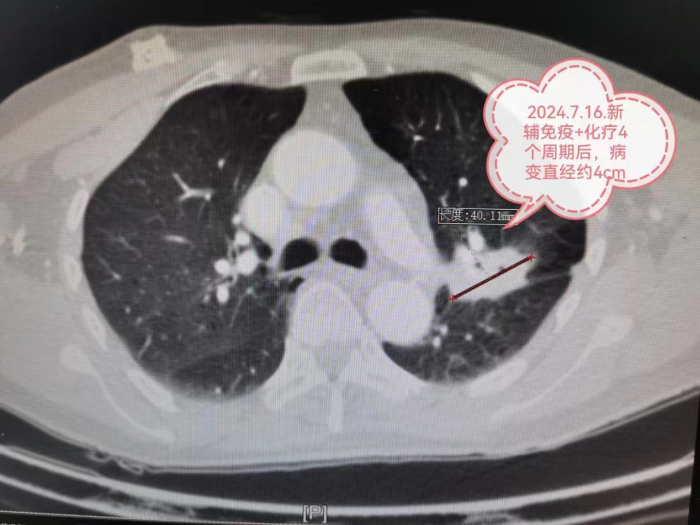

经过4个周期的新辅助化疗联合免疫抑制治疗后,肿瘤最大直径由77mm明显缩小到40mm,分期由IIIA期降为IIA期。

心胸外科陈光春主任团队召开病例讨论会,大家一致认为新辅助化疗联合免疫抑制治疗效果明显,患者获得了根治性手术机会。经过严谨、全面的术前准备后,最终为严先生成功实施单孔胸腔镜下肺癌根治术,手术圆满成功。

术后病理检查显示:经过之前的新辅助治疗,病变的大小由77mm缩小到40mm(缩小约48%),经过显微镜观察,实际的癌细胞仅仅残存6%,也就是说40mm肿块里面94%的组织已经没有癌细胞啦,医学上称这种情况叫做主要病理学缓解(MPR)。

新出现的基因靶向治疗和免疫治疗特点:副作用小,患者才可以长期使用;药物有效率高,使用以后肿瘤就容易变小甚至消失。所以,基因靶向治疗和免疫治疗以更高效的速率杀灭肿瘤细胞,原本一个非常广泛发展的肿瘤,可以被安全地缩小到一定程度范围,而且还不会伤及身体的根本。手术不再是晚期患者不可企及的奢望,而是顺其自然地照进了现实。比如本文中的IIIA期肺癌患者,且肿瘤包裹左上肺重要血管,几乎没有手术机会,或者被迫切除左全肺,术后生活质量差。在免疫药+化疗药的协同作用下,肿瘤直径缩小48%,分期由IIIA期降为IIA期,于是手术机会来了,而且只切除了左上肺,保留住了左下肺,术后生活质量相对切除左全肺更好。手术切除后肿瘤残余比例不足10%,实现了主要病理缓解(MPR)。